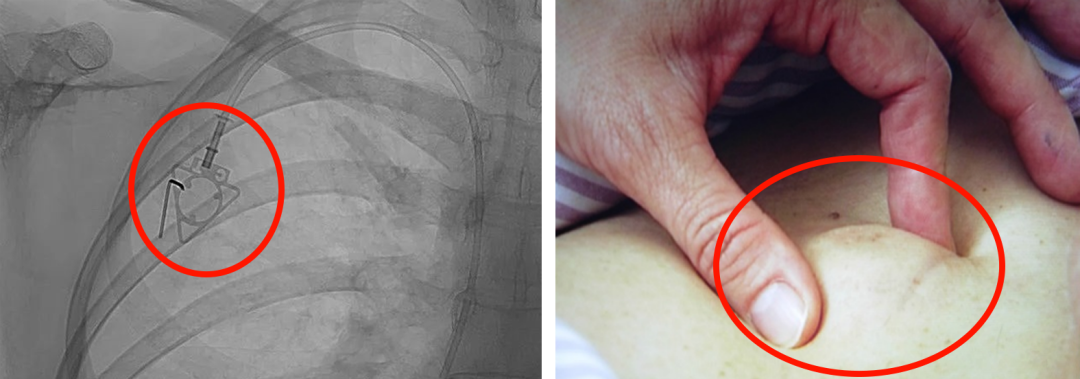

輸液港,臨床上也稱為PORT,是為了減輕藥物對(duì)患者血管刺激而置入體內(nèi)的專業(yè)輸液裝置。它分為三部分:無(wú)損傷針、置入靜脈的導(dǎo)管、埋藏在皮下與輸液針連接的注射座(港體)。注射座連接插入大靜脈的導(dǎo)管形成長(zhǎng)期血管通路,發(fā)揮類似港口的作用,故稱作“輸液港”。